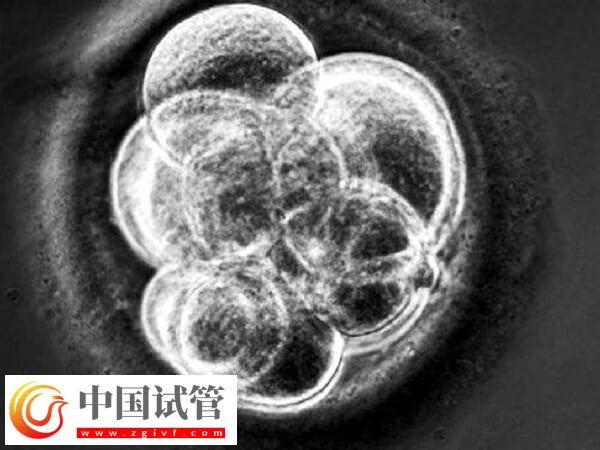

胚胎因素

優(yōu)質(zhì)胚胎在試管移植之后,染色體發(fā)生異變、遺傳物質(zhì)提讓改變等也會(huì)導(dǎo)致三代試管胚胎不著床;